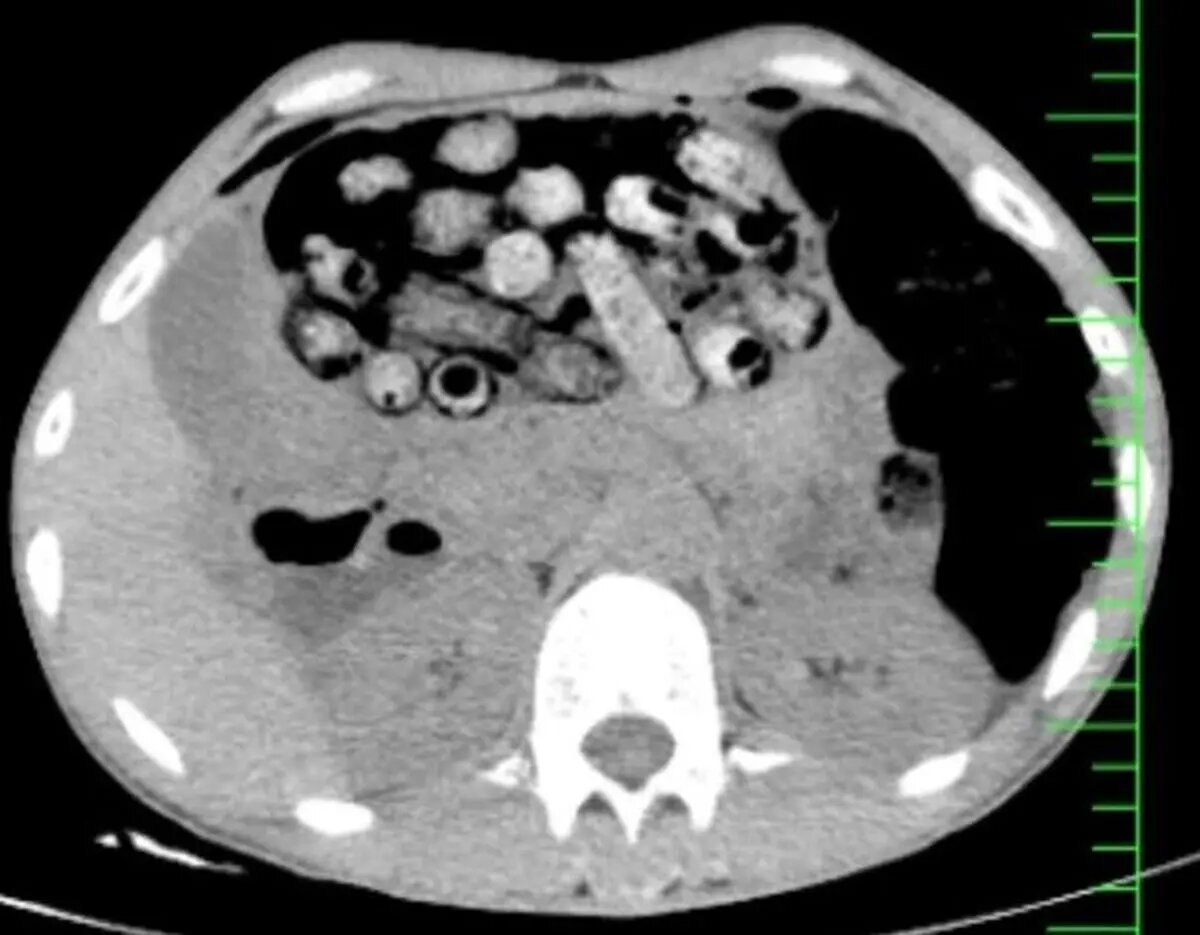

به گزارش ایسنا، براساس اطلاعات اولیه مأمور همراه، بیمار پیش از مراجعه، اقدام به بلع تعدادی بسته محتوی مواد مخدر کرده بود. در پی انجام تصویربرداری فوری، تعداد زیادی بسته مشکوک در معده و روده کوچک و بزرگ وی مشاهده شد.

با توجه به خطر بالای پارگی احتمالی بستهها و بروز عوارض تهدیدکننده حیات، بیمار بلافاصله به اتاق عمل منتقل شد و جراحی سنگین وی از ساعت سه بامداد آغاز شد.